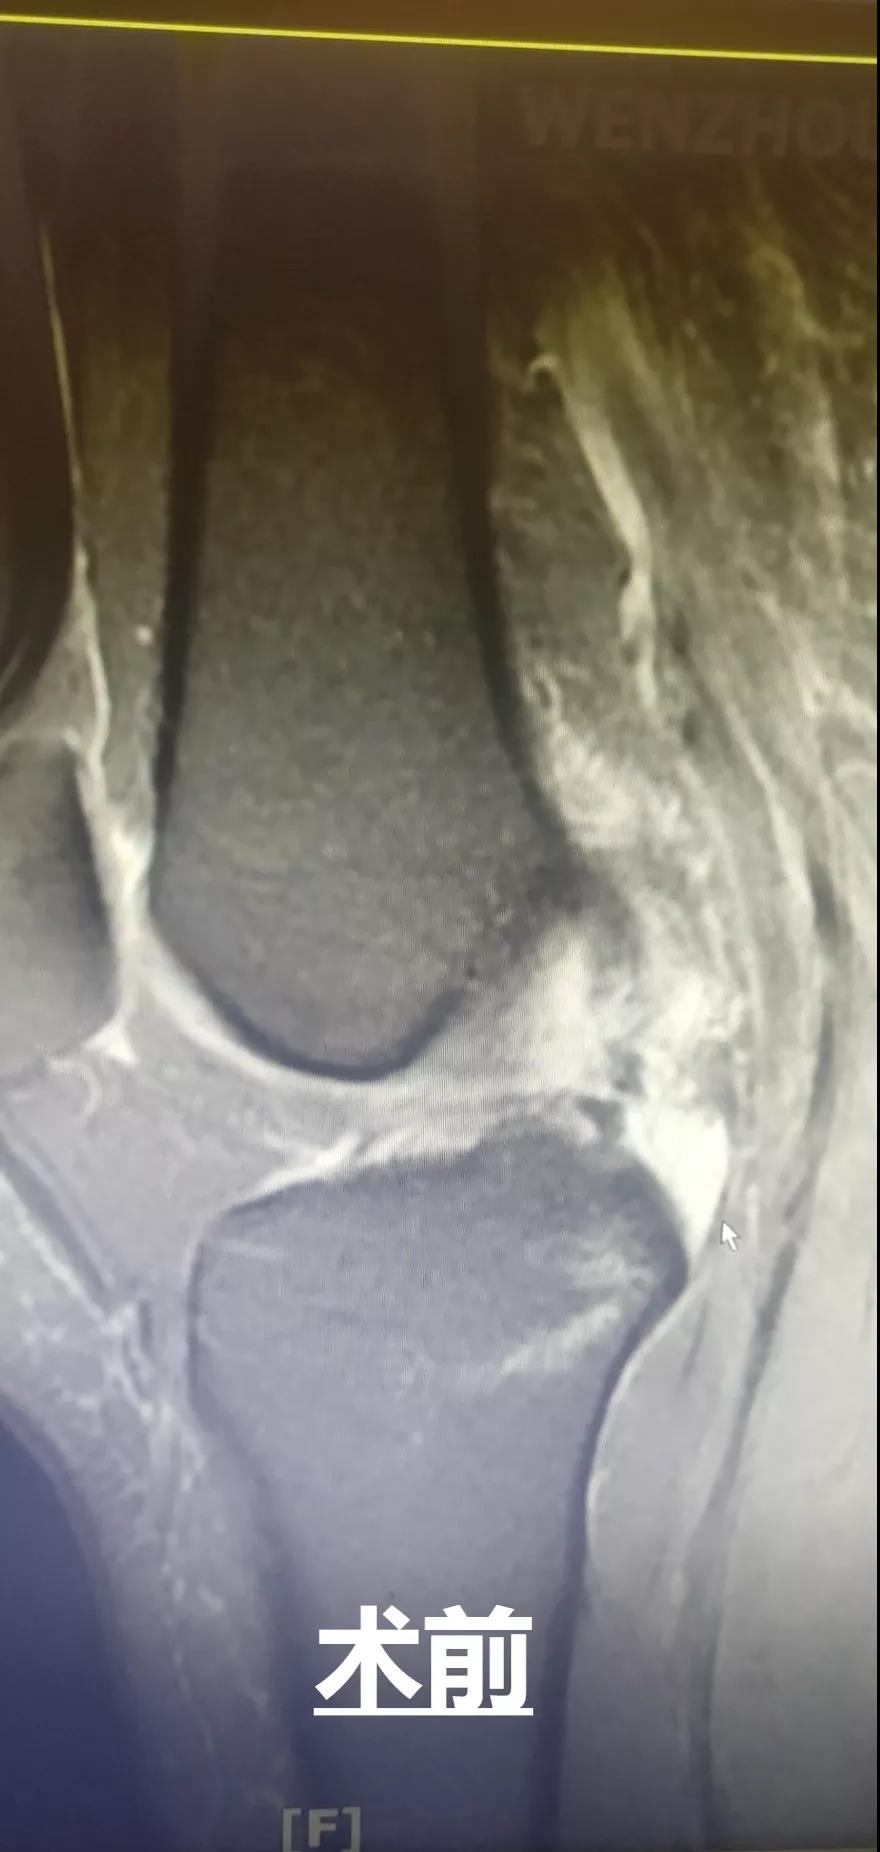

此外,和平國(guó)際醫(yī)院關(guān)節(jié)鏡微創(chuàng)團(tuán)隊(duì)還完成了一例交叉韌帶修復(fù)術(shù)。此手術(shù)采用三個(gè)約0.5cm的微小創(chuàng)口,于脛骨結(jié)節(jié)處進(jìn)行定位,后鉆通脛骨隧道,應(yīng)用多種袢鈦板進(jìn)行多位置固定,手術(shù)過(guò)程短,創(chuàng)口小,術(shù)后效果好,患者十分滿意。